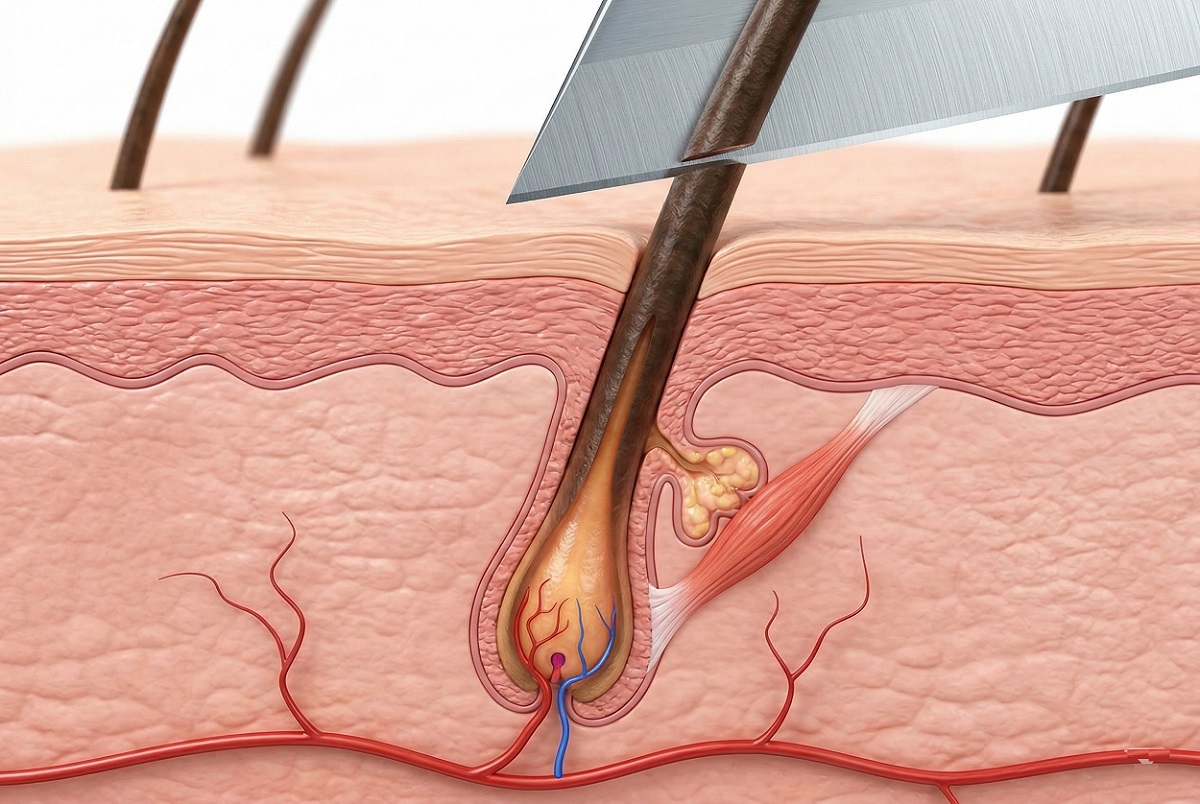

2. Миф о том, что бритьё делает волосы гуще

Распространено мнение, что бритьё делает волосы более густыми, жёсткими или тёмными.

На самом деле бритва срезает только стержень волоса - его мёртвую часть, расположенную над поверхностью кожи. Рост происходит в волосяном фолликуле, находящемся в дерме, и не зависит от срезания.

Иллюзия «утолщения» объясняется просто: у сбритого волоса отсутствует естественный сужающийся кончик, поэтому он кажется более жёстким и плотным. Кроме того, новые волосы ещё не подверглись воздействию солнца и могут выглядеть темнее.